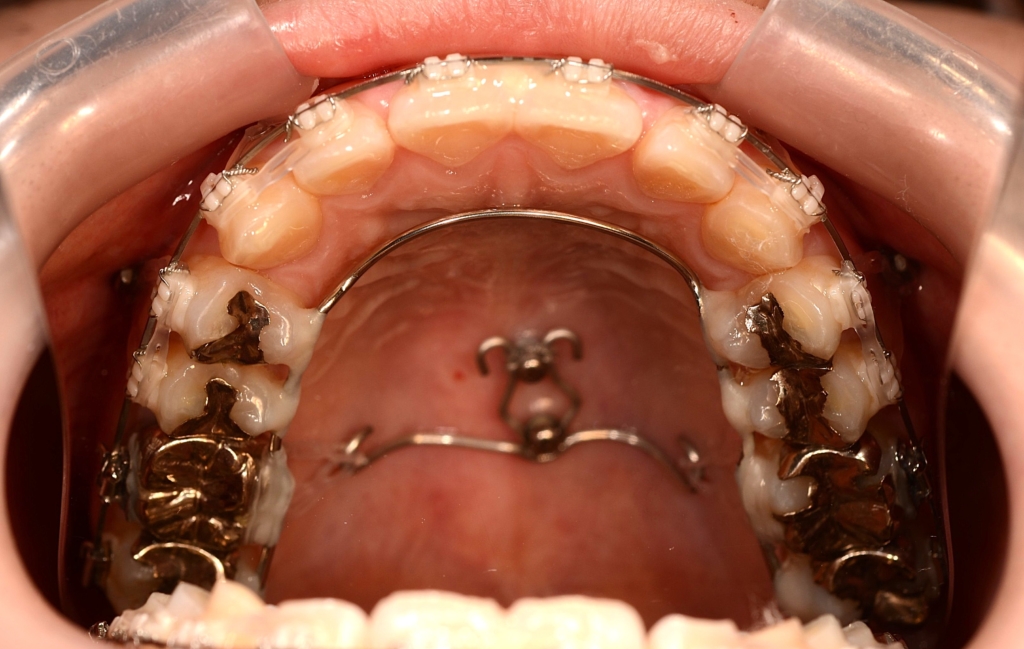

アンカースクリュー:

上顎に計6本(前歯に2本、奥歯に2本、口蓋に2本)使用

ステップが進み歯列が揃ったところで、ガミースマイル改善のために、上顎にアンカースクリューを植立することにしました。

部位は、上顎の口蓋の真ん中、臼歯部(左右側とも)と前歯部の頬側、になります。

アンカースクリューを用いて矯正力を加えることで、上顎歯列全体を圧下させて、ガミースマイルの改善を図ります。